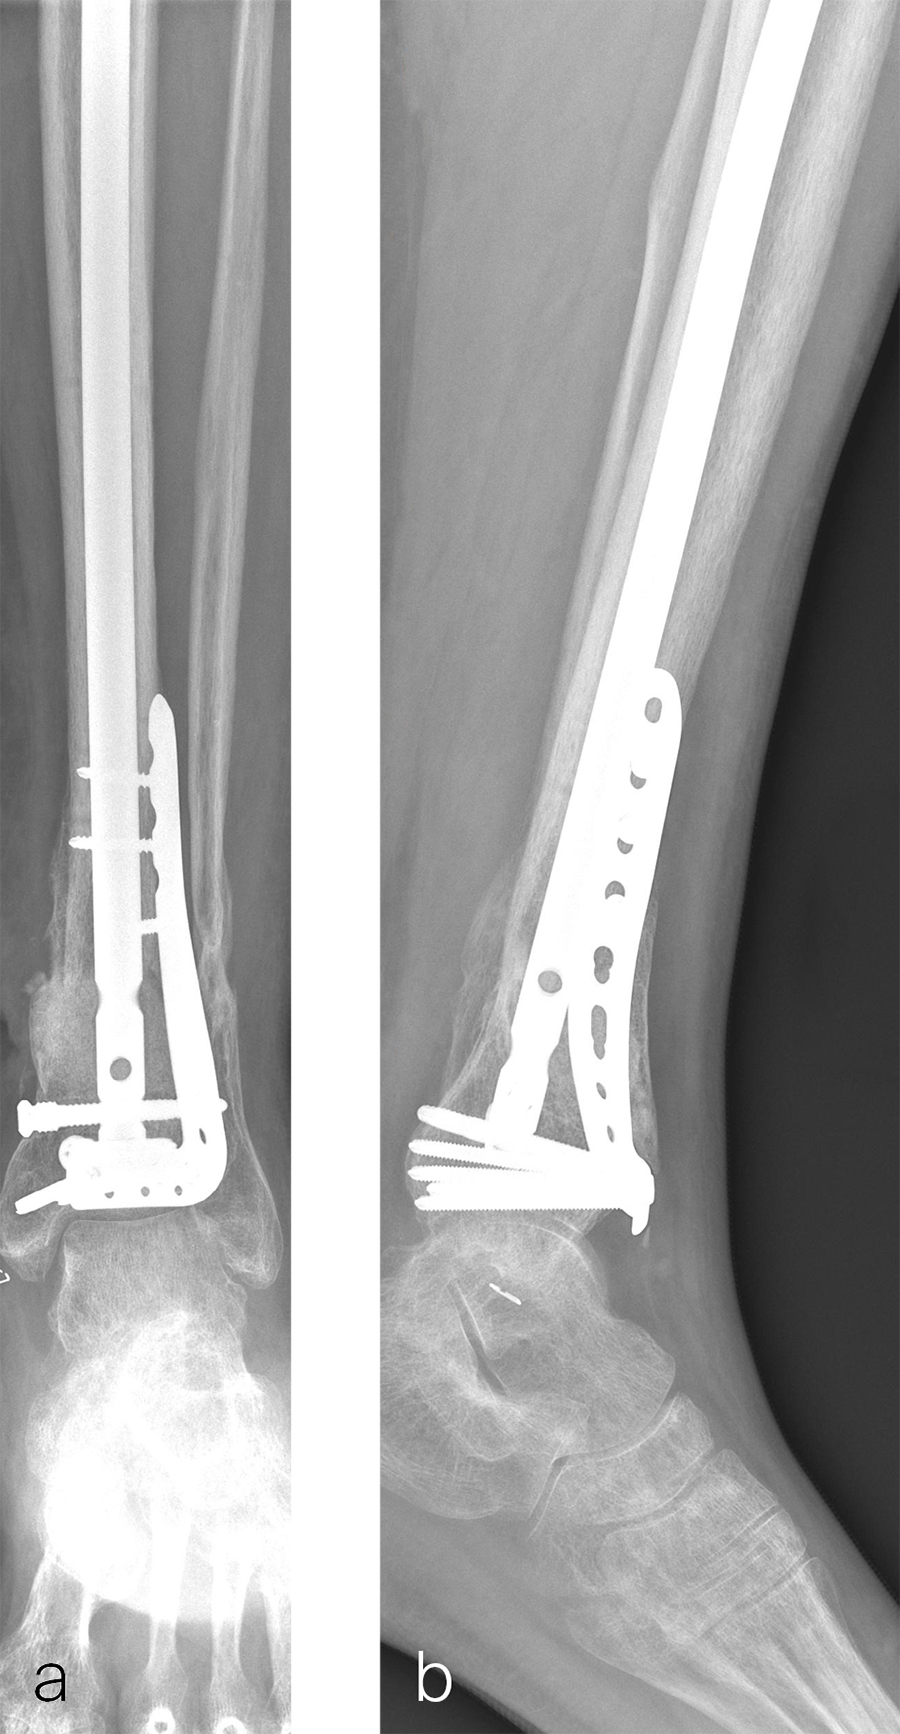

Two months later, the patient had a staged cement spacer removal and hardware removal followed by a new spacer placement (Fig 4). When microbiological cultures were negative for 5 days he was taken to the OR for definitive fixation and bone grafting. RIA bone graft from the ipsilateral femur was taken, a new anterior lateral plate was placed with an adjunct IM nail (and angle stable screws) as the distal plafond was now one articular block (Fig 5).

The patient has been followed up monthly for more than 5 months and has shown continued consolidation of the bone defect (Fig 6). Furthermore, he is weight bearing as tolerated without significant pain. The leg lengths are equal and the range of motion at the ankle is 10/25 dorsiflexion/plantarflexion. He has mild pain over the ankle joint but no pain at the fracture site.